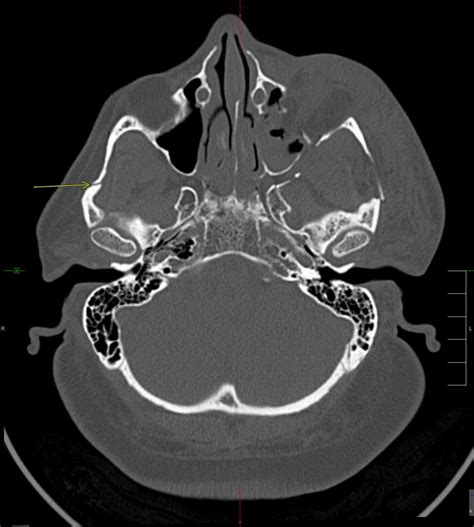

The classification system developed by René Le Fort remains the gold standard for describing patterns of maxillary fractures. While a Lefort I fracture affects the lower maxilla and a Lefort II involves the mid-maxilla and nose, the Lefort III fracture is defined by a transverse fracture line that traverses the frontozygomatic suture, the orbit, and the nasofrontal suture. Essentially, the entire facial skeleton is disconnected from the skull, creating a "floating" midface.

Due to the complexity of these injuries, patients often present with a characteristic "dish-face" deformity, where the middle of the face appears sunken or pushed backward. The diagnostic process is rigorous, often requiring high-resolution CT scans to map the displacement of bone fragments precisely before surgical planning can begin.